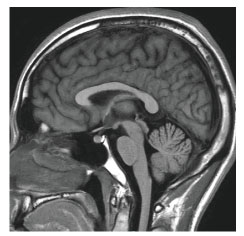

当院のMRI画像集